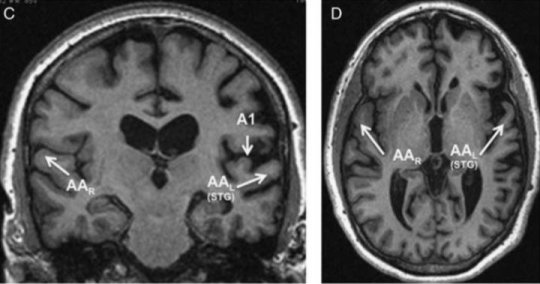

“It doesn’t happen that often that you just get an impairment in one area,” Weintraub said, explaining that the brain is compartmentalized so that different networks share the job of seemingly easy tasks, such as reading a word and being able to say it aloud. “The fact that only the auditory words were impaired in these patients and their visual words were untouched leads us to believe we’ve identified a new area of the brain where raw sound information is transformed into auditory word images.”